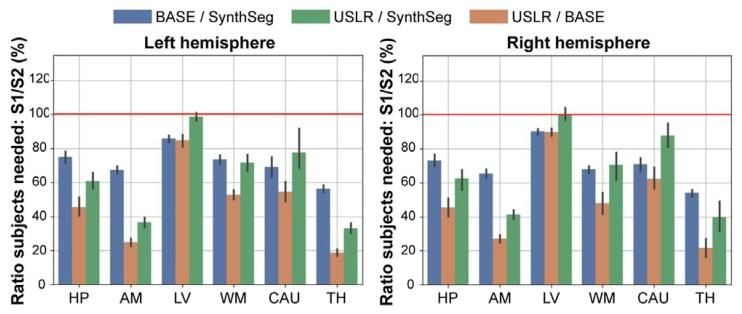

Fig. 10. Power analysis showing the fraction of required subjects comparing segmentation methods S1 and S2. In blue, S1=BASE and S2=SynthSeg; in green S1=USLRand S2=SynthSeg; and in orange, S1=USLR and S2=BASE. A value < 100% indicatesthat S1 needs less subjects than S2 for given study specifications (power, target effectsize, target power, etc.). The red line indicates that the same number of subjects arerequired between S1 and S2. BASE refers to longitudinal processing of timepoints usingthe baseline image as template. In the 𝑥-axis, we show the result of considering differentsubcortical region as primary outcome of the study

图10 效能分析:展示分割方法S1和S2所需受试者比例的对比。蓝色曲线代表S1=BASE与S2=SynthSeg的对比;绿色曲线代表S1=USLR与S2=SynthSeg的对比;橙色曲线代表S1=USLR与S2=BASE的对比。当数值<100%时,表明在给定研究规格(效能、目标效应量、目标检验效能等)下,S1所需的受试者数量少于S2。红色线表示S1和S2所需的受试者数量相同。BASE指以基线图像为模板对时间点进行的纵向处理。x轴展示将不同皮质下区域作为研究主要结局指标的分析结果。